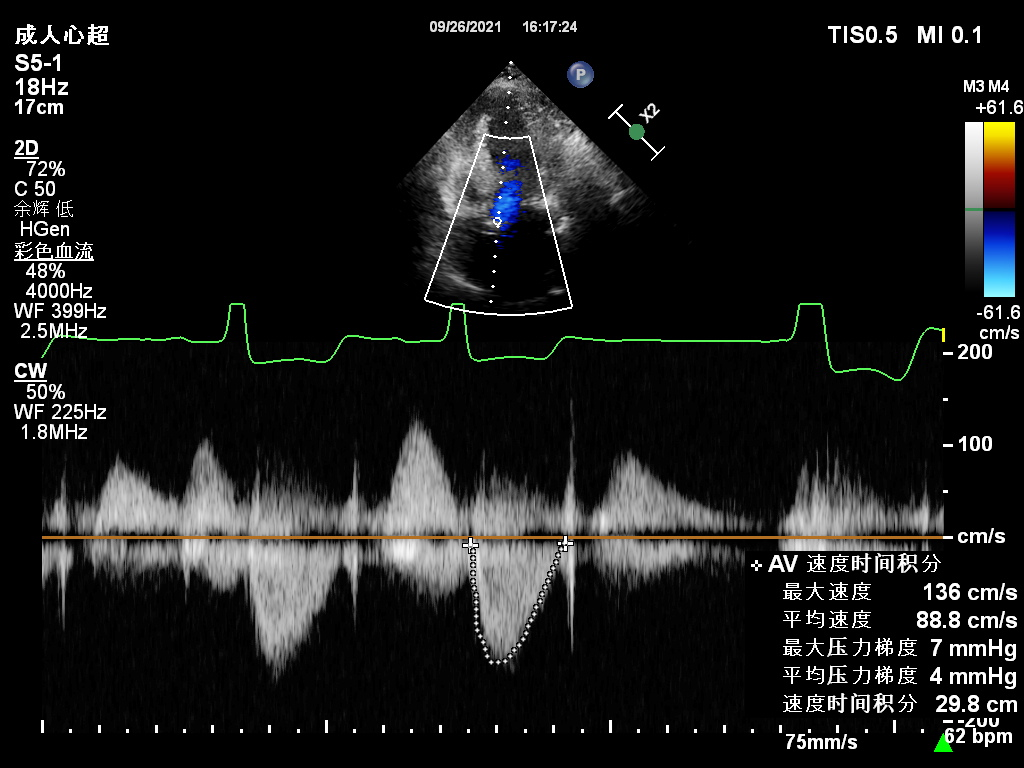

术后超声

主动脉瓣最大流速由5.03 m/s下降至1.36 m/s,平均压差由74mmHg下降至4mmHg,未见主动脉瓣反流